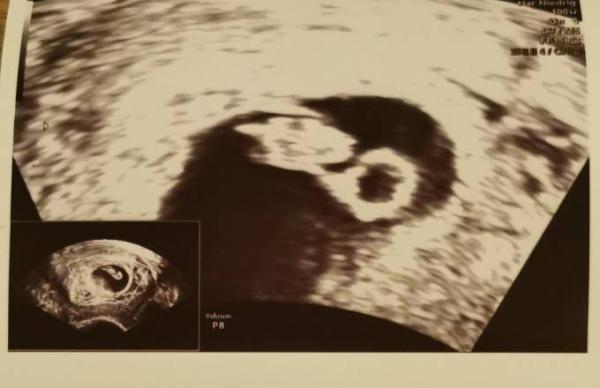

Hallo ihr lieben. Da ich gestern Abend wieder eine leichte Schmierblutung hatte, habe ich dann heute doch bei der Ärztin angerufen und somit hatten wir dann heute den ersten Termin. Es ist alles da wo es hingehört und das hat auch schön geschlagen. Laut meiner Rechnung müsste ich bei 7+0 sein, laut Ultraschall bin ich bei 6+6 also passt es auch. Und die Blutung ist aufjedenfall nicht aus der Gebärmutter sondern Scheinbar einfach nur vom Muttermund, da ja alles mehr durchblutet ist, kann es schonmal passieren. Ich bin auf jeden Fall beruhigt und supi happy

Bild zu Update von uns < 3 - Forum für Juli - Mamis